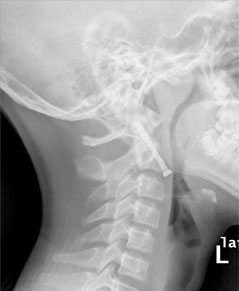

病例2  颈2齿状突骨折前路空心螺钉内固定术。

患者13岁,男性,颈2齿状突骨折。

患者受伤后2天入院,入院时四肢肌力2-3级

术后第3天

术后3个月,骨折愈合,患者四肢肌力恢复正常。